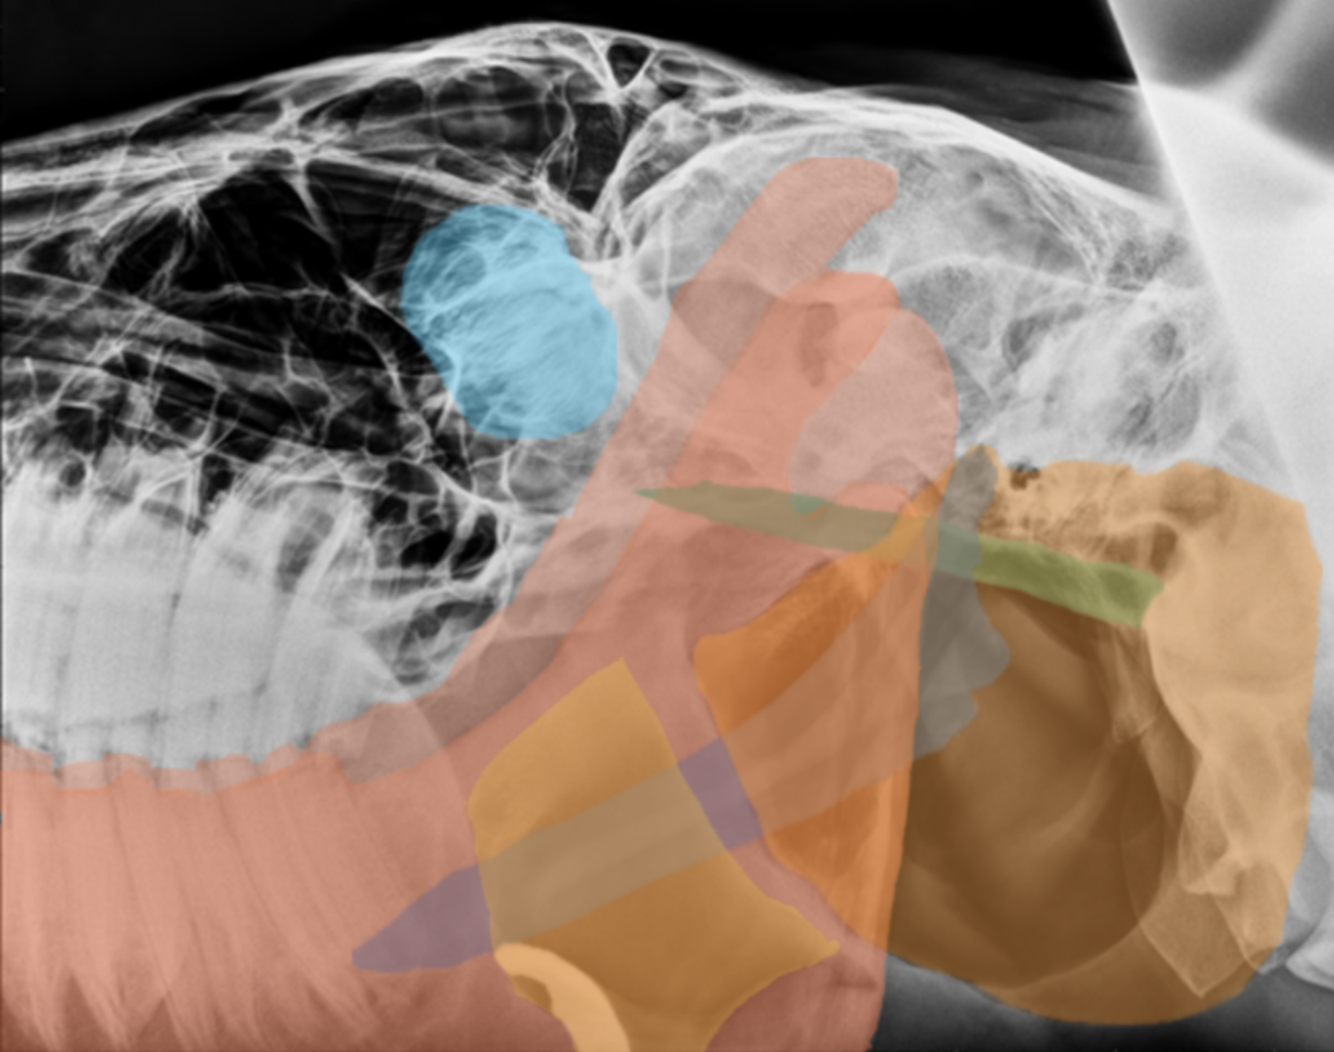

dorsoventral equine skull

red: mandibles

blue: nasal turbinates (conchi)

orange: vomer

yellow: maxillary sinus

pink: styelohyoid bones

dark blue: maxillary teeth